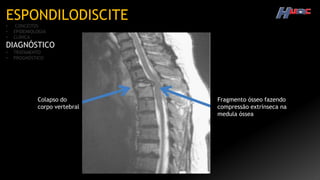

RM

Colapso do

corpo vertebral

Fragmento ósseo fazendo

compressão extrínseca na

medula óssea